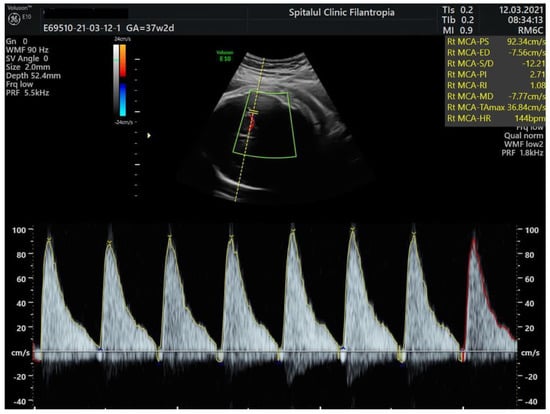

We present the case of a 32-year-old, para 1, gravida 2 woman with blood type B Rh positive who was admitted to our unit at 37 weeks and 2 days for reduced fetal movements. Until this hospitalization, her pregnancy was uneventful. Prenatal screening tests were unremarkable, and Group B Streptococcus and serologies for congenital infections were negative. On physical examination, there were no other maternal signs or complaints no uterine contractions, and blood pressure and heart rate were normal. Cervix was long and closed with no signs of vaginal bleeding. Ultrasound examination at admission showed an estimated fetal weight of 2900 g, normal amniotic fluid, and normal flow in the umbilical artery, but abnormal Doppler studies in the fetal middle cerebral artery showed (MCA) peak systolic velocity (PSV) of 109.9 cm/s (Figure 1). For the gestational age, this value exceeded 1.5 MoM and was in keeping with severe fetal anemia. Fetal hemoglobin level was estimated based on this measurement at 4.5 g/dL according to the Fetal Medicine Foundation prediction of anemia algorithm. (https://fetalmedicine.org/research/assess/anemia, accessed on 12 March 2021).

Peak systolic velocity of the middle cerebral artery (MCA-PSV) in Doppler measurement plays an important role in assessing and monitoring suspected fetal anemia [12]. FMH is associated with MCA-PSV ≥ 1.5 multiple median (MoM), as it correlates with moderate or severe fetal anemia. Doppler evaluation of fetal MCA-PSV is based on the principle that MCA-PSV increases with decreasing fetal hemoglobin levels [13].

Figure 1. Doppler studies of mean cerebral artery (MCA) in a term baby showing increased peak systolic velocity (PSV) and absent end-diastolic flow.

MCA-PSV—109.9 cm/s (>1.5 MoM; estimated fetal Hb 4.5 g/dL) (Figure 1)